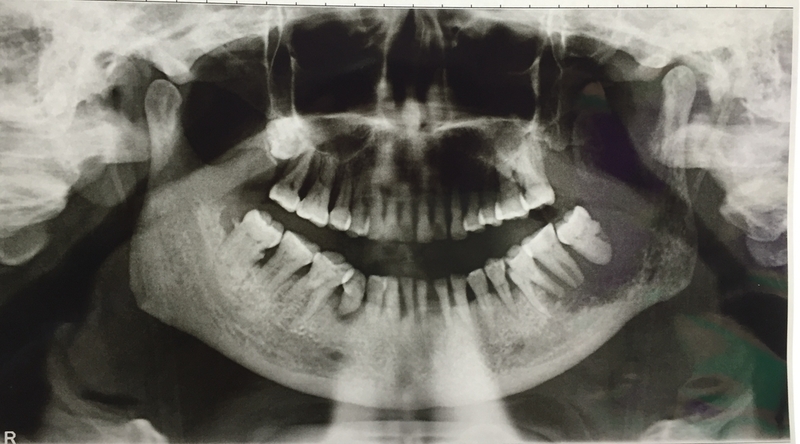

Dental care and oral hygiene largely remains an undiscussed topic, with few people aware of the risks associated with poor dental hygiene. The National Oral Health Care Programme, which falls under the care of the Ministry of Health and Family Welfare (MoHFW), stated that despite the fact that several dental diseases have been burdening the country in the last three decades, little attention has been paid to tackling these issues. Tooth decay, dental caries, and periodontal diseases have been noted to be high among the Indian population, and yet oral care is ignored so often.

In 2018, the National Institute of Cancer Prevention which falls under the Indian Council of Medical Research (ICMR), released a study that showed that oral cancer cases in India had spiked in a span of six years. The institute noted that around 12 lakh cases of cancer were reported across the country in 2018, rising from 10 lakh reported cases in 2012. Reports have stated that anywhere up to as much as 85% of the entire population is susceptible to a dental disease, with India being referred to as the world’s “capital” for oral cancers.